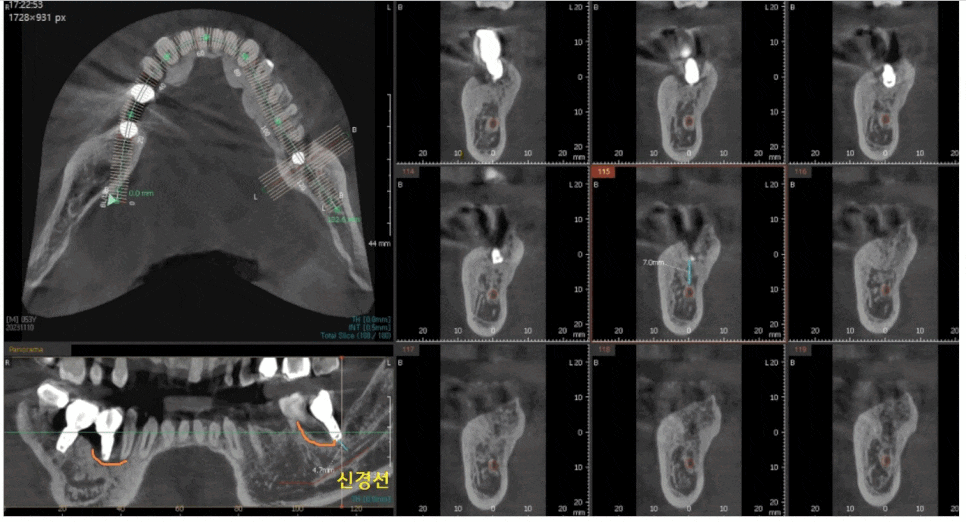

x-ray 상에서 잇몸 뼈가 녹은 경우에는

주변보다 까맣게 표시되는데요.

좀더 자세한 분석을 위해 ct를 촬영

역시나 까맣게 녹은 부분이 관찰이 되죠?